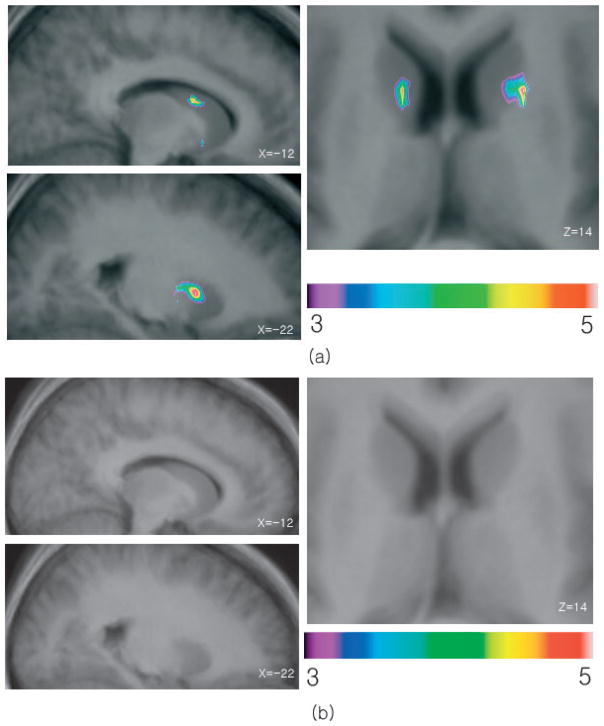

cTBS of the left DLPFC affected MCST-induced striatal dopamine release resulting in a bilateral increase in [11C]raclopride BP in the striatum as compared to control condition (vertex–cTBS) (Fig. 5). More specifically, [11C]raclopride BP increased by 14.67% (vertex condition, 2.22 ± 0.12; DLPFC condition, 2.56 ± 0.20) in the ipsilateral caudate nucleus (x = −12, y = 5, z = 15; t = 4.6, cluster size 48 mm3) and by 12.59% (vertex condition, 2.50 ± 0.08; DLPFC condition, 2.80 ± 0.10) in the contralateral caudate (x = 18, y = 8, z = 14; t = 4.8, cluster size 40 mm3; Figs 4 and 5). A significant area of change in [11C]raclopride binding was also observed in the ipsilateral putamen, 12.98% (vertex condition, 3.29 ± 0.13; DLPFC condition, 3.69 ± 0.18) with its peak (t = 4.6) at coordinates x = −21, y = 6, z = 3. No changes in BP were detected in the contralateral putamen or anywhere in the ventral part of the striatum.

Fig. 5.

(a) Comparison between left DLPFC and vertex stimulation (control condition). Sagittal (x = −12 and x = −22) and axial (z = 14) sections of the statistical parametric map of the change in [11C]raclopride BP overlaid upon the average MRI of all subjects in stereotaxic space. The figure displays the significant areas of striatal dopamine changes during MCST performance after left DLPFC stimulation compared to vertex stimulation (control). (b) Comparison between right DLPFC and vertex stimulation showing the lack of changes in [11C]raclopride BP.

Fig. 4.

In the lower panel [11C]raclopride binding potential (mean ± SE) during MCST performance after left DLPFC stimulation and vertex stimulation (control), from left caudate (P < 0.05), right caudate (P < 0.05) and left putamen (P < 0.05), extracted from a spherical region of interest centered at the x, y and z coordinates of the statistical peak revealed by the parametric map. In the upper panel the solid dots represent individual BPs.